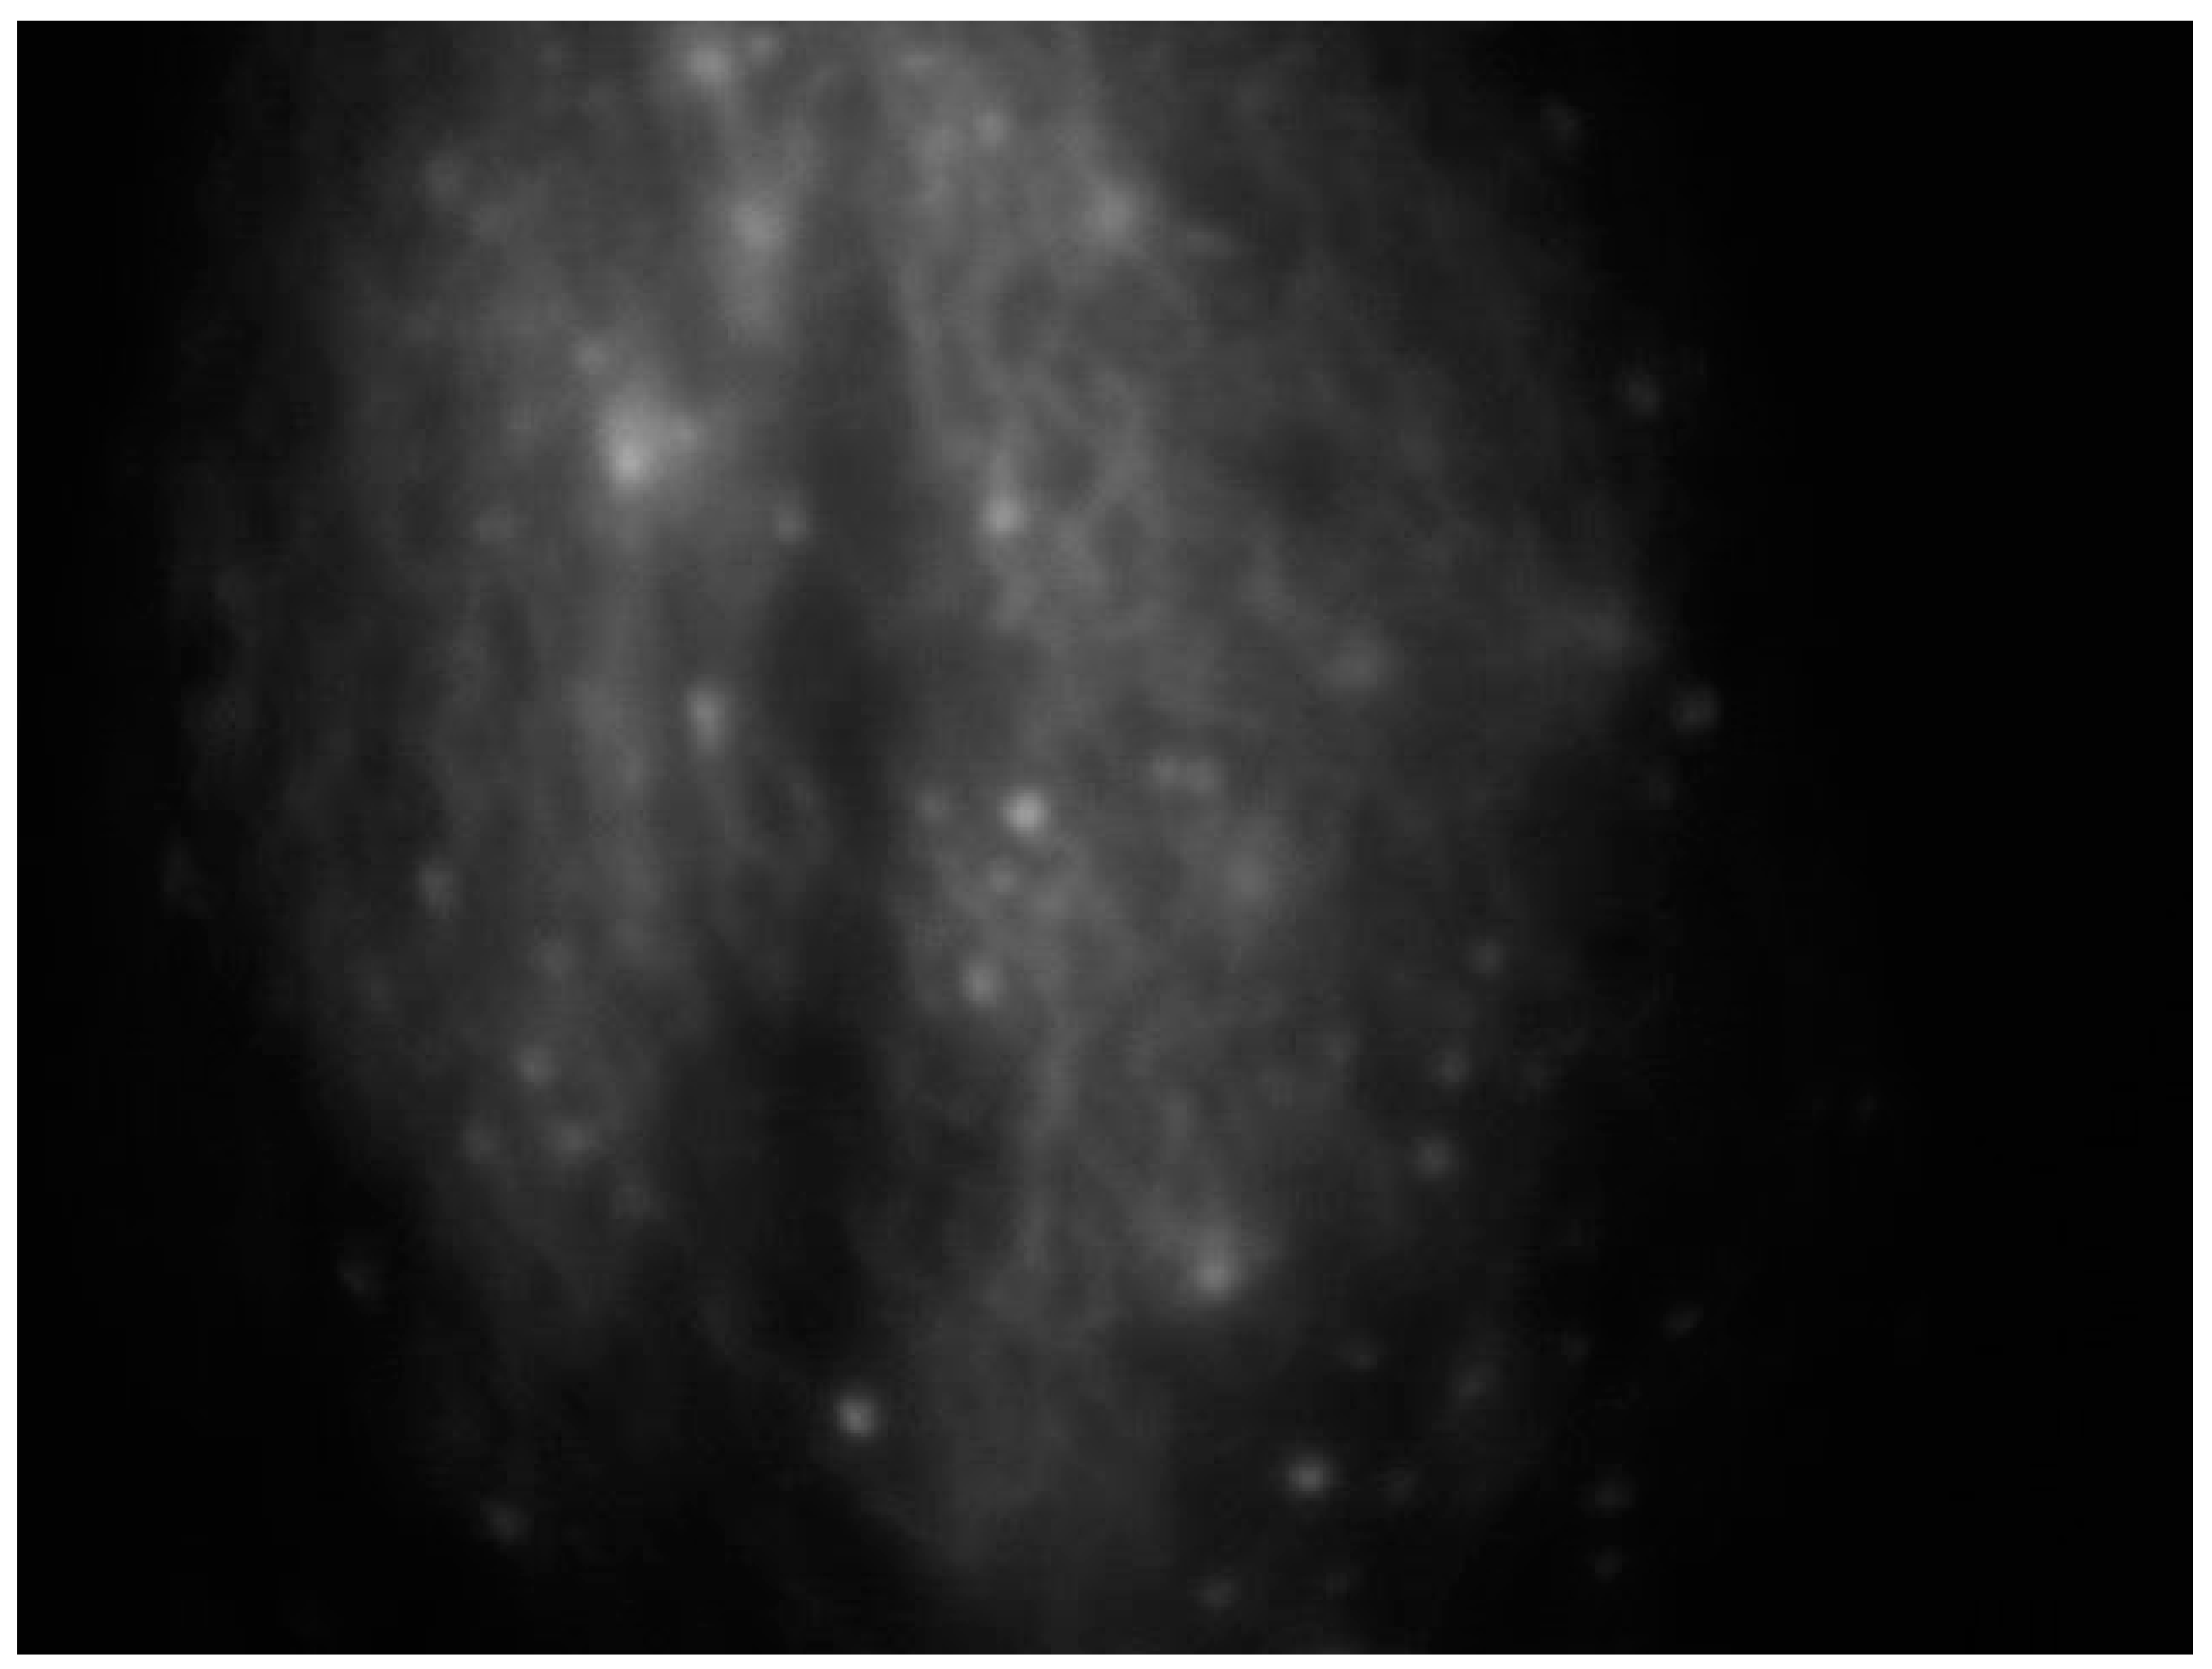

2.2. Near-Infrared Fluorescence Imaging

An effective substitute for assessing lymphatics is near-infrared fluorescence imaging, which uses a contrast media injected intradermally instead of a radionuclide to access the primary lymphatics beneath the epidermis, helping to assess lymphatic anatomy and function [38] (Figure 2).

Figure 2.

Intraoperative ICG lymphography for lower limb lymphatic vessel evaluation in a patient with post-prostatectomy secondary lymphedema.